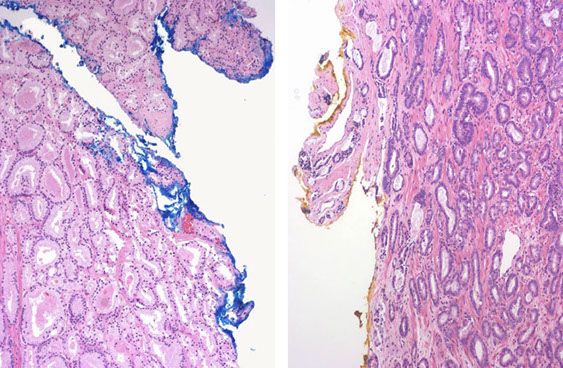

Prostatic Duct AC

Ductal Adenocarcinoma

- ductal AC usually centrally located in periurethral region and sampled on TURP

-- PIN uncommon in periurethral region and infreq seen on TURP

- ductal AC usually has true papillary fronds c well-formed fibrovascular core, whereas HG-PIN more freq reveals micropapillary fronds c tall columns of epithelium w/o fibrovascular stalks

- ductal AC freq has comedonecrosis, which can be extensive

-- HG-PIN lacks comedonecrosis

- ductal AC can consist of large or back-to-back glands, whereas glands c PIN are of the size and distribution of b9 glands